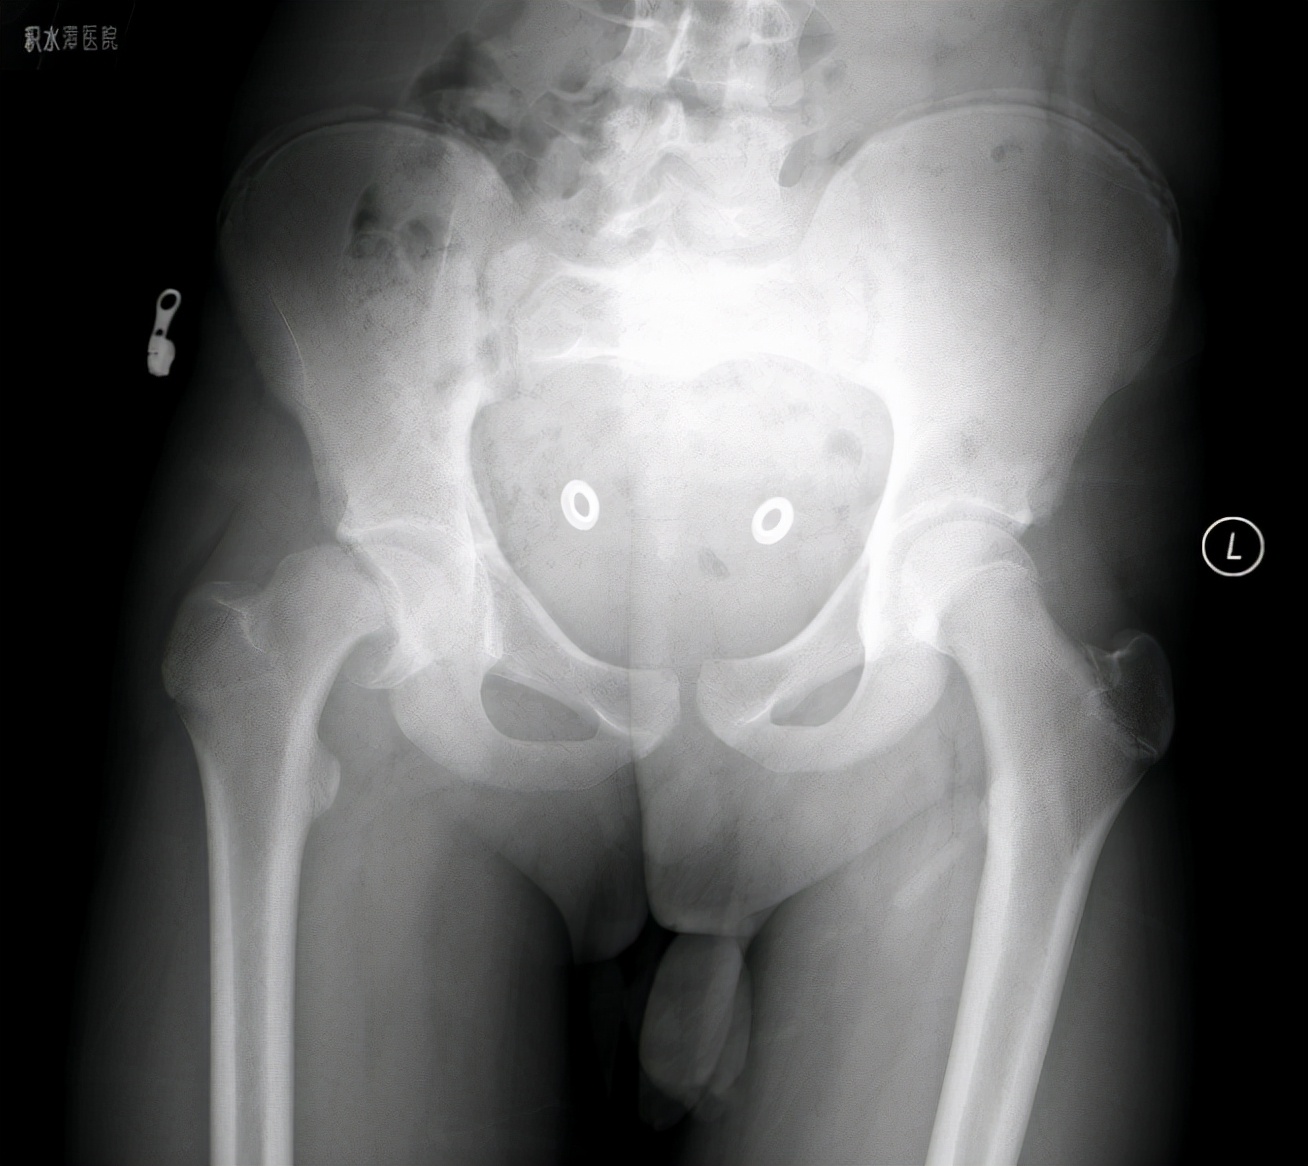

病例2 男,14岁,右侧重度SCFE,行闭合复位,经皮空心钉固定术

病例2 术后17个月复查,X线示位置良好,无股骨头缺血坏死发生